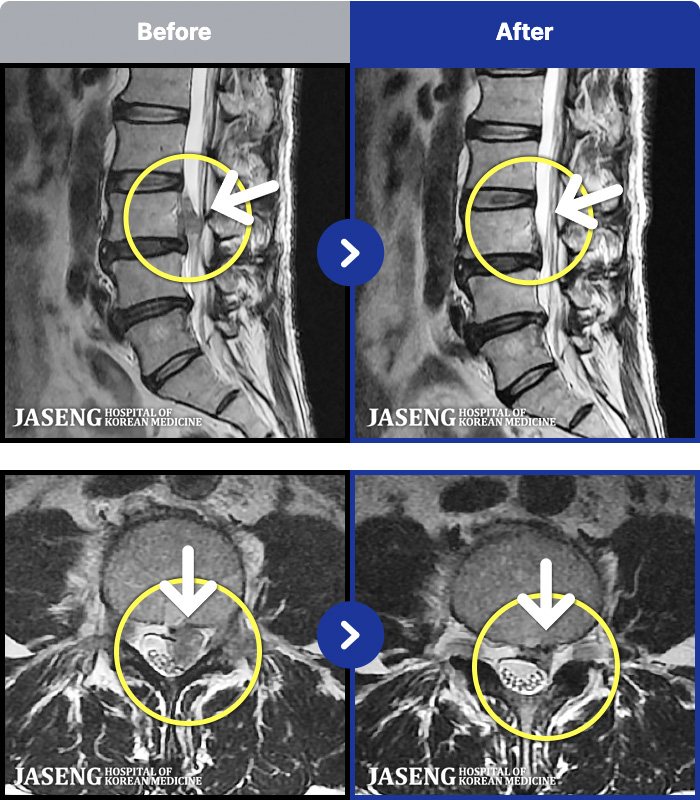

MRI ġ

101 MRI ũ ʸ Ȯϼ.